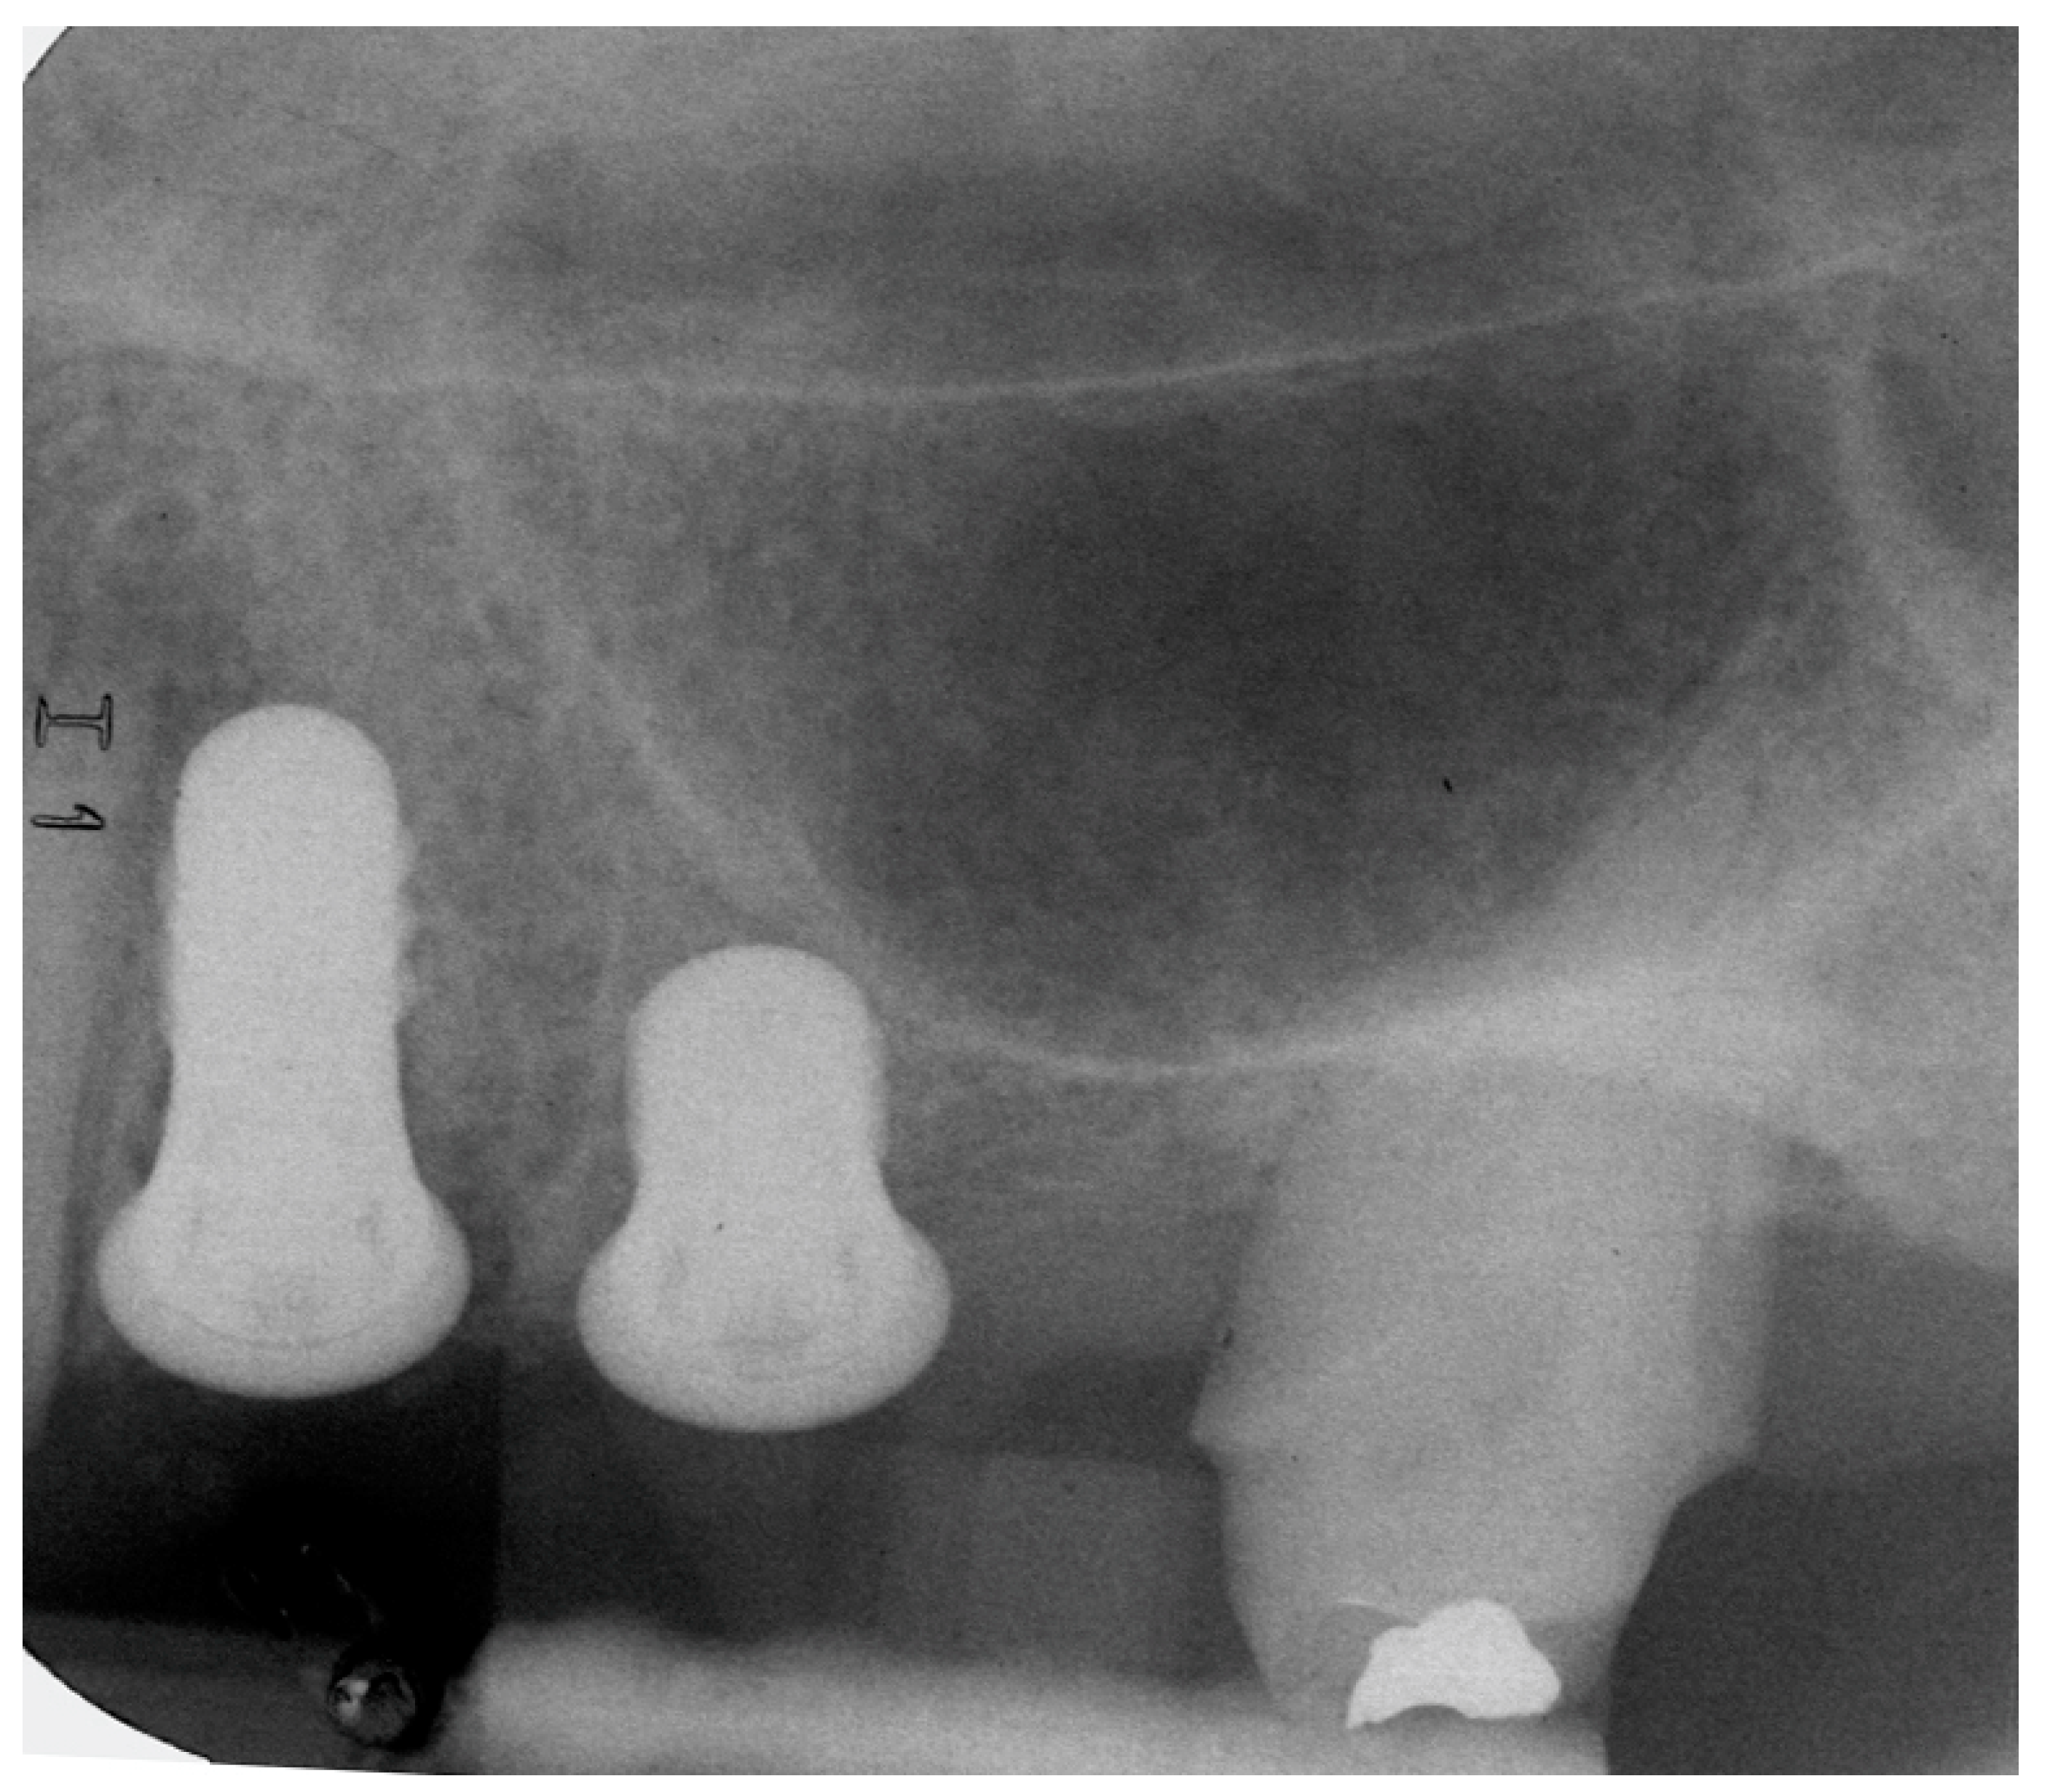

4.1. Marginal Bone Level (MBL)

4.2. Bone tissue remodeling (MBL change)